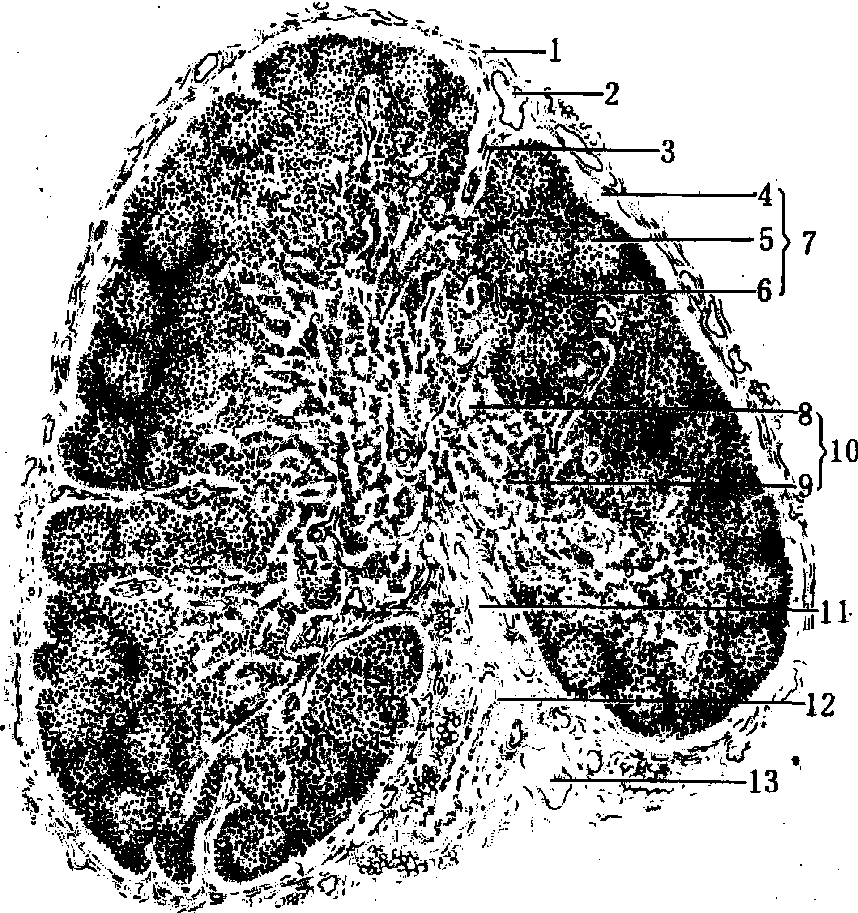

组织结构 被膜由薄层结缔组织构成,伴随血管和神经的结缔组织伸入淋巴结内形成小梁。小梁及其分支交织成粗大网架,实质充填于网眼中,可分为皮质与髓质(图2)。

图 2 淋巴结通过门部纵切面

1. 被膜; 2.输入淋巴管; 3. 小梁; 4. 皮质淋巴窦; 5淋巴小结; 6. 副皮质区; 7. 皮质; 8. 髓窦; 9. 髓索10. 髓质; 11. 门部; 12. 血管; 13. 输出淋巴管